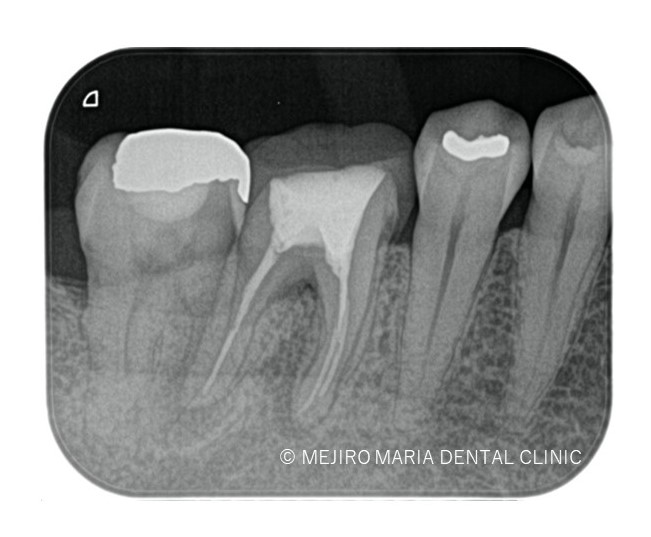

※画像は術前レントゲン写真と口腔内写真

5年前に治療した歯に違和感を感じることを主訴に来院される。当該歯は1年前に大きく腫れた時を境に徐々に調子が悪くなっているとのこと。

右の口腔内写真赤矢印部分には限局的な歯周ポケット10mmを確認し、歯根破折の可能性を疑わせる。

治療はすべて歯科用顕微鏡下(マイクロスコープ)にて行い、前回の治療で充填されている材料をすべて除去した後に破折診査をおこなった。歯科用顕微鏡(マイクロスコープ)下でも遠心根に破折線は見つけられず、通法通り根管治療を終了した。

3ヶ月後のレントゲン撮影にて根尖病変の縮小、ならび違和感の消失を確認。今後最低2年間の経過観察(1年に1回)を行い、根尖周囲組織の治癒を確認していく。